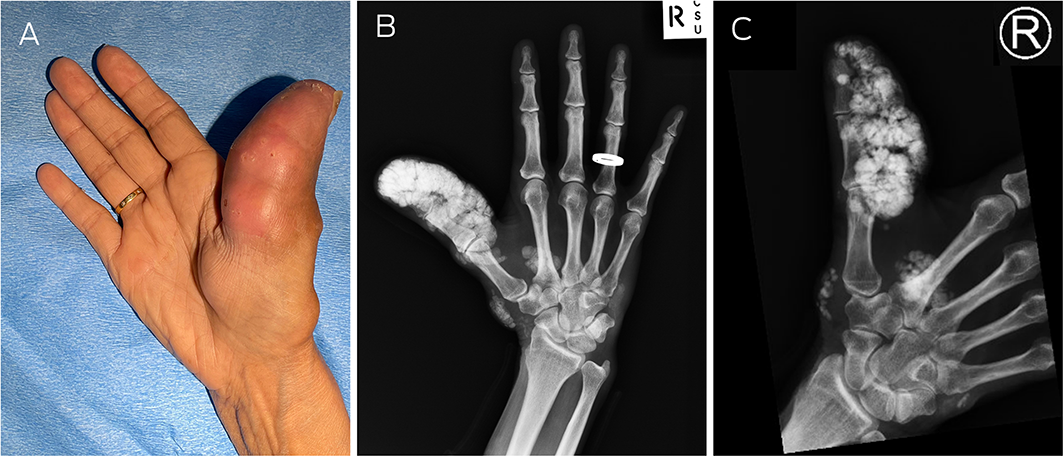

Calcinosis cutis of the thumb